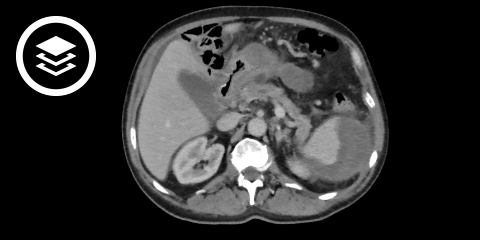

CT-Fallbeispiel

DICOM-Modelle können auf Mobilgeräten leider nicht angezeigt werden.

MRT und CT können – vor allem im Frühstadium bei akuten Flüssigkeitsansammlungen – zur genaueren Lokalisation bzw. differentialdiagnostischen Abgrenzung herangezogen werden.

- Bildquelle DICOM-Viewer: Datensatz freundlicherweise zur Verfügung gestellt durch die Klinik für diagnostische und interventionelle Radiologie, St. Vinzenz Hospital Köln